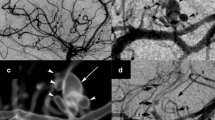

6 Pathway from Ganglia to Cerebral Arteries: Innervation of the Circle of Willis

The pathogenesis of arterial ischemic stroke caused by an infectious agent requires that the pathogen be carried to the cerebral arteries. For herpesviruses such as VZV, the conduit is a nerve fiber. Evidence regarding the innervation of the cerebral arteries comes predominantly from experiments in an array of animal models. The most well-studied pathway is centered on the trigeminal ganglion (cranial nerve V). Afferent fibers from the trigeminal ganglion travel to the circle of Willis and its numerous arterial extensions (Fig. 4). One early study to define innervation pathways was carried out by damaging the ophthalmic and maxillary branches of the ophthalmic nerves in monkeys and observing the sites of Wallerian degeneration with the internal carotid artery, the middle cerebral artery and the basilar artery (Simons and Ruskell 1988). This study confirmed an even earlier investigation using neuronal tracing with wheat germ agglutinin conjugated with horseradish peroxidase (WGA-HRP) in the rat model. When WGA-HRP was injected into the trigeminal ganglion, labeled nerve fibers were found in arteries of both the anterior circulation (the internal carotid, middle cerebral, anterior cerebral and posterior communicating arteries) as well as the posterior circulation (posterior cerebral, superior cerebellar and basilar arteries) (Arbab et al. 1986).

Innervation of the cerebral arteries by afferent fibers from the trigeminal ganglion. a During varicella, virus is carried retrograde from vesicles on the face to the ophthalmic division of the trigeminal ganglion, where virus usually enters a latent state. b Trigeminal ganglion. c Upon reactivation, virus can travel via afferent fibers to the anterior cerebral artery (ACA), the middle cerebral artery (MCA), the posterior communicating artery (PCOA), the posterior cerebral artery (PCA), the superior cerebellar artery (SCA) and the basilar artery (BA). The most afferent fibers travel to the MCA and the second most fibers travel to the ACA; far fewer fibers travel to the SCA and the BA

When the tracer was applied to the middle cerebral artery, labeled trigeminal cells were present in the ipsilateral trigeminal ganglion. Similarly, when tracer was applied to the middle meningeal artery, labeled calls were found in the ipsilateral trigeminal ganglion. Another study using a similar approach also found evidence of trigeminal innervation of the middle meningeal artery, a branch of the external carotid artery that supplies the meninges (dura mater) (Mayberg et al. 1984). A different group used a retrograde axonal tracer called True Blue to study the innervation of the middle cerebral artery in the rat. They confirmed that the True Blue tracer was carried to the trigeminal ganglion from the middle cerebral artery (Edvinsson et al. 1989).

Even though the most studied pathway is the trigeminal ganglion, the superior cervical ganglion also appears to innervate cerebral arteries, particularly, but not exclusively, the posterior circulation. Both the sensory trigeminal ganglion and the sympathetic superior cervical ganglion harbor latent VZV. Similar tracing techniques were used to study innervation by the superior cervical ganglion. When WGA-HRP was injected into the basilar arteries of cats, the greatest number of labeled cells were found in the superior cervical ganglion (Keller et al. 1985).When the reverse experiment was performed by injection of WGA-HRP into the superior cervical ganglion, labeled nerve fibers were found in the anterior communicating, anterior cerebral, posterior communicating, superior cerebellar and rostral basilar arteries. A similar study was performed in the dog after resection of the superior cervical ganglion and observing Wallerian degeneration. Degeneration of nerve fiber was documented in both the anterior circulation (anterior communicating, anterior cerebral, middle cerebral, posterior communicating arteries) and posterior circulation (posterior cerebral, superior cerebellar and basilar arteries) (Sato et al. 1980).

Collectively, these animal experiments suggest the anterior circulation may be innervated by the sensory trigeminal ganglion and the posterior circulation by the sympathetic superior cervical ganglion. Hence, either could potentially serve as a conduit for VZV to cause a cerebral arteritis.